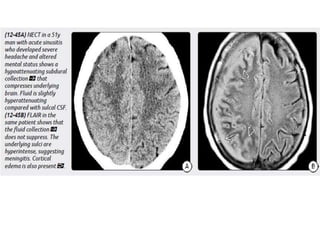

Imaging

NECT scans may be normal or show a hypodense extraaxial collection

that demonstrates peripheral enhancement on CECT.

Bone CT should be evaluated for signs of sinusitis and otomastoiditis.

MR is the procedure of choice for evaluating potential empyemas. T1

scans show an extraaxial collection that is mildly hyperintense relative to

CSF.

SDEs are typically crescentic and lie over the cerebral hemisphere. SDEs

often extend into the interhemispheric fissure but do not cross the midline.

EDEs are biconvex and usually more focal than SDEs. EDEs may cross

the midline, confirming their epidural location